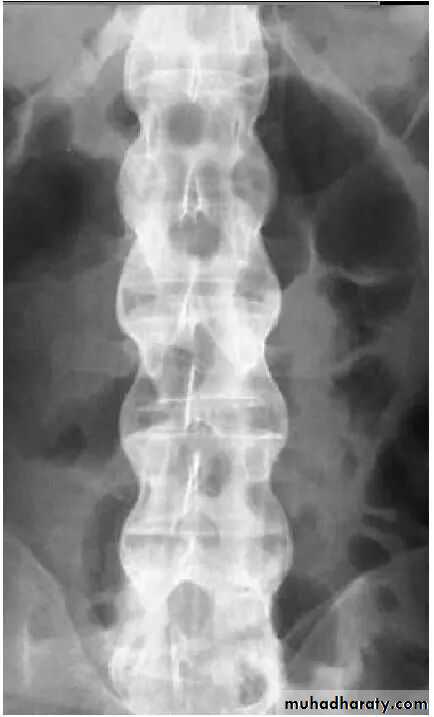

Spine

• Progressive mineralization of Sharpey’s fibres to form osseous bridging syndesmophytes

• Bamboo spine

• Dagger sign apperance

Bamboo spine